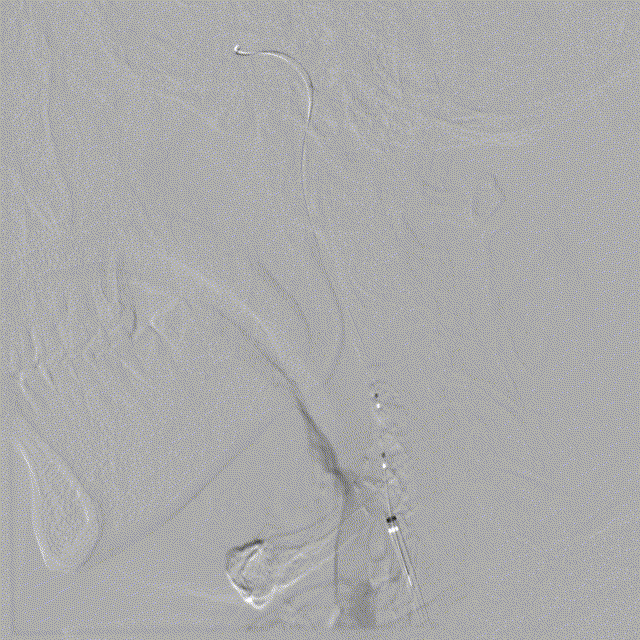

左侧颈总动脉正侧位造影

造影导丝和Sim2造影导管将7F EasyRadial™输送导管置于颈内动脉:

路径图下,微导丝越过颈内开口狭窄段达岩骨段,取2.5*15mm 颅内球囊扩张导管送至左侧颈内动脉开口狭窄处给予预球囊扩张成形术。

球囊扩张后狭窄改善。

输送保护伞至颈内动脉C1末端平直段。

沿保护伞导丝送入7.0*50mm Wallstent颈动脉支架至颈内动脉开口处。

准确定位后释放支架。

支架释放后造影显示残余狭窄40%。

再次沿保护伞导丝送入4.0*25mm 颅内球囊扩张导管,越过支架送至颈内动脉开口狭窄最严重处给予球囊后扩张成形术。

术后造影显示支架内无明显残余狭窄,颅内血管无明显栓塞。